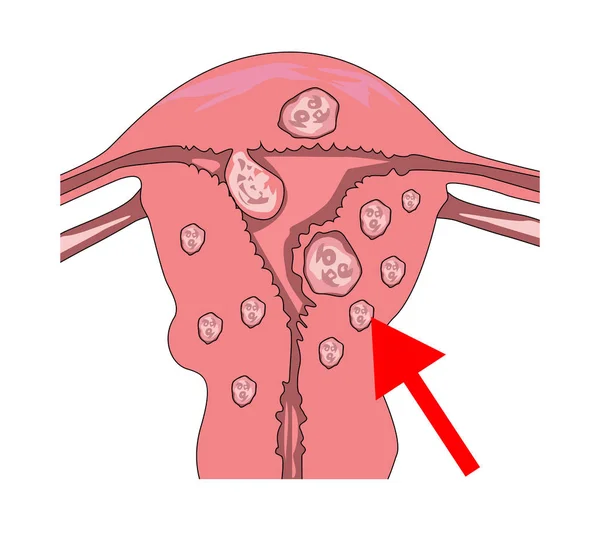

Cette tumeur bénigne affectant environ 50% des femmes âgées de 30 à 50 ans. Aussi appelé fibrome utérin, le fibrome se développe à partir du tissu musculaire.

Le myome est appelé une tumeur bénigne, qui se développe dans les tissus de l'utérus. La tumeur est semblable à la spire noueuse et peut être localisée à la fois sur.

Aussi appelé fibrome, le myome utérin est une pathologie gynécologique, généralement bénigne. Elle concerne environ un tiers des femmes en âge de procréer. Cette petite.

Qu'est-ce qui provoque les myome ? La cause exacte des fibromes est inconnue, mais les hormones et les facteurs de croissance semblent jouer un rôle. La croissance des.

Qu’est-ce qui provoque les myomes? La cause exacte des fibromes est inconnue, mais les hormones et les facteurs de croissance semblent jouer un rôle. La.